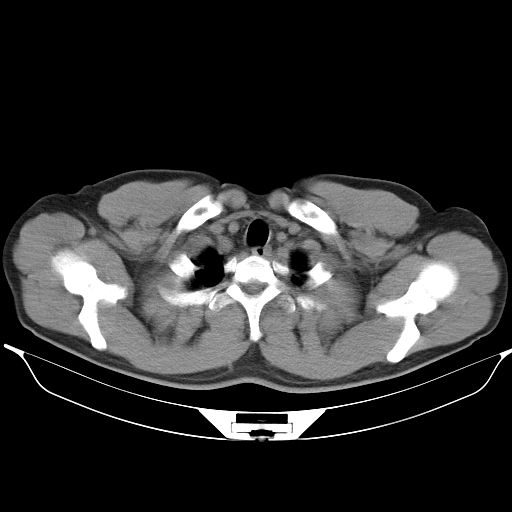

标题: CT25490:男,40岁,体检发现;无其它不适。 [打印本页]

标题: CT25490:男,40岁,体检发现;无其它不适。

支持 !考虑右下肺周围性肺癌并肺内多发转移,纵隔淋巴结转移,(气管前腔静脉后,隆突下,主动脉弓下都有了)